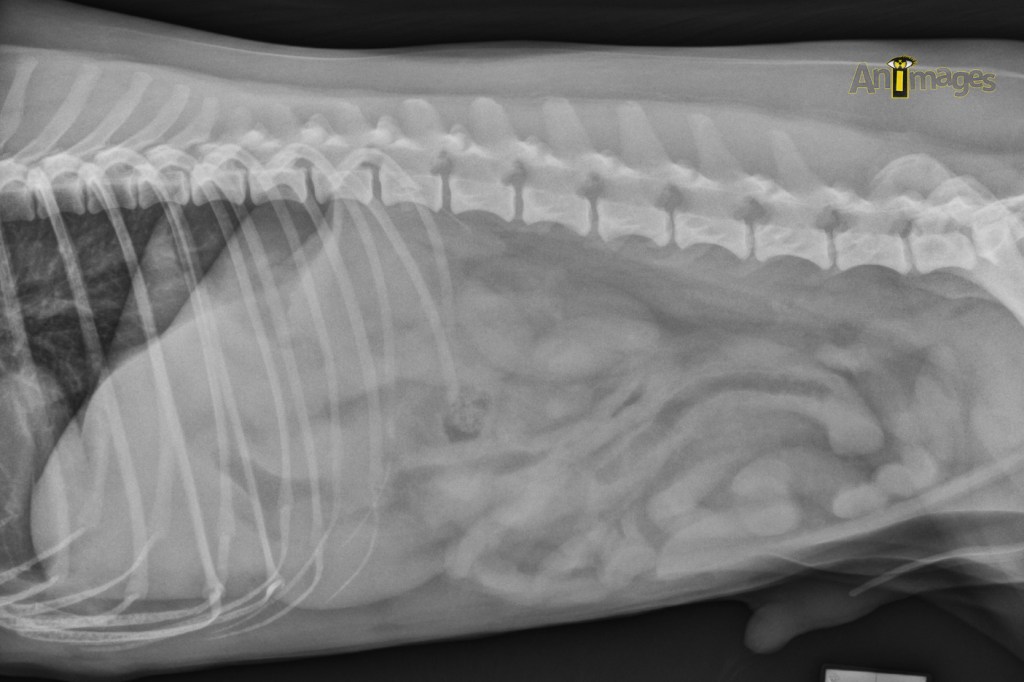

Latérale gauche